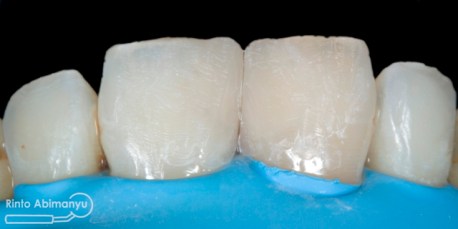

Selesai penambalan dan sebelum dilakukan konturing dan pemolesan

Kemudian dengan bantuan pensil dibuat panduan surface texture, dan mulai dibentuk dengan bur ukuran fine (strip merah) kecepatan rendah… Setelah tekstur selesai kemudian mulai dilakukan pemolesan, saya menggunakan Enhance (Denstply) bentuk point untuk awal dilanjut Soflex Spiral (3M) dan terakhir menggunakan buff…

Alhamdulilah ini hasil akhir dari gigi 11 dan 21…

Gigi 11 dan 21 setelah selesai konturing dan pemolesan